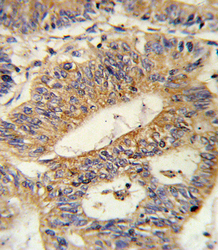

- Experimental details

- Formalin-fixed and paraffin-embedded human colon carcinoma reacted with IL17RB Antibody , which was peroxidase-conjugated to the secondary antibody, followed by DAB staining. This data demonstrates the use of this antibody for immunohistochemistry; clinical relevance has not been evaluated.